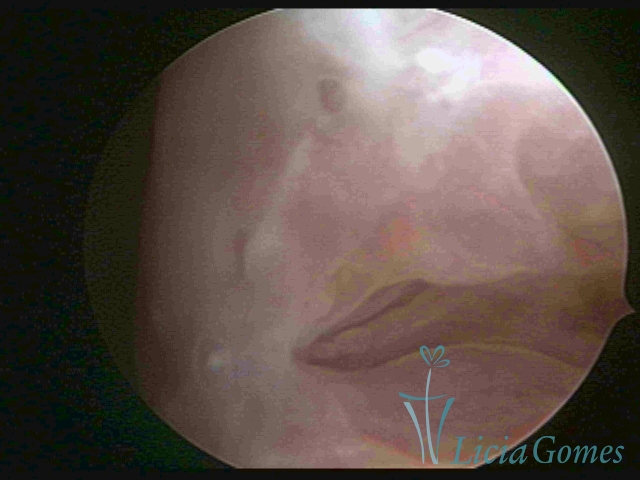

Terceira porção ou porção superior

Apresenta a mucosa com a superfície lisa e pouco vascularizada até a altura do orifício interno